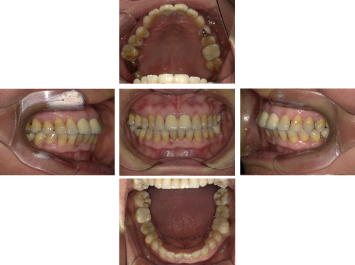

30代 女性 インプラント治療(鎮静療法)

| 主訴 | 口腔内かなり状態悪く、これから先しっかり噛んで食事ができるようにインプラントを入れたい。 |

| 部位 | 左上3,5,7、右下5 |

| 治療期間 | 約11ヶ月 |

| 費用 | ¥2,145,000(税込) |